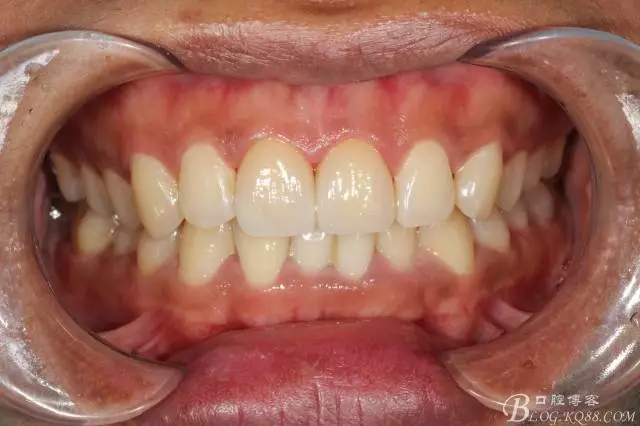

粘接完成即刻照

即刻照局部放大

兩周后復(fù)查(訴11遇冷有點(diǎn)不適,因11備牙有點(diǎn)多,露牙本質(zhì)。囑注意不要進(jìn)食過(guò)冷過(guò)熱食物。癥狀約一個(gè)月后逐漸消失。)

兩周復(fù)查局部放大